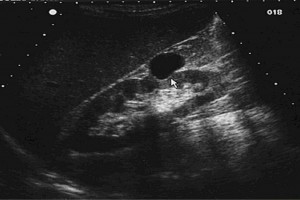

Diplomados en Ultrasonografía